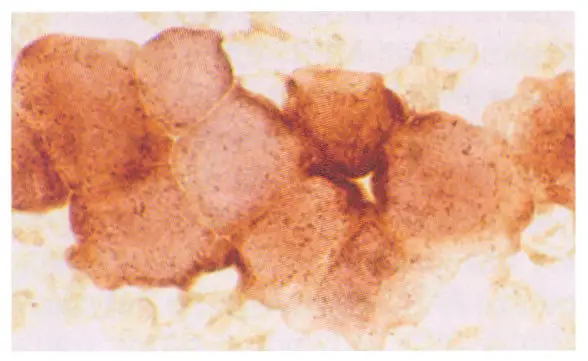

某一急性白血病的骨髓抹片, myeloperoxidase ( MPO ) stain 結果如圖①, nonspecific esterase ( NSE ) stain 結果如圖②,其最可能為下列何種疾病?

圖① Myeloperoxidase (MPO) stain:

- 觀察:細胞核呈紫色,細胞質中可見散在的藍黑色/深色顆粒。部分細胞有顆粒,部分細胞顆粒較少或不明顯。

- 意義:MPO 染色陽性代表細胞含有 Azurophilic granules,主要見於髓系細胞(Myeloblasts, Promyelocytes)。然而,圖中細胞的顆粒密度並未達到 AML M3(急性前骨髓細胞白血病)典型的「密集充滿(packed)」程度,顯示雖有髓系分化或部分陽性,但非強烈陽性的 M3 特徵。在 AML M5 中,Monoblasts 通常為 MPO 陰性或呈現微弱/細顆粒陽性。

**圖② Nonspecific Esterase (